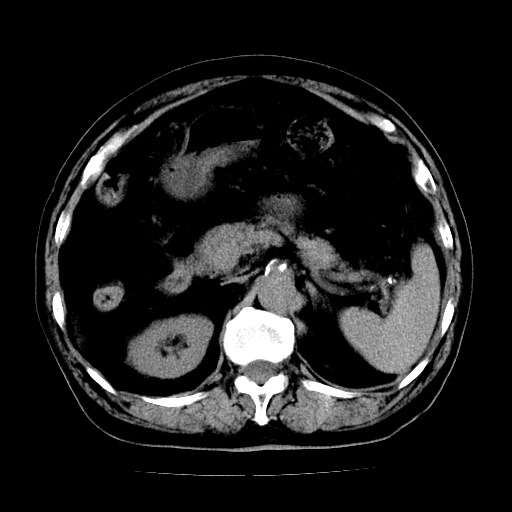

男,71岁,皮肤黄染四天。

肝内外胆管及胆总管上段扩张,考虑为梗阻所致,建议mrcp检查。

考虑胆总管癌并肝内外胆管扩张。

胆管癌并肝内外胆管扩张。

支持考虑胆总管癌并肝内外胆管扩张。 局部应薄扫。心包钙化。

胰腺上端胆总管内见软组织影,强化不明显,结合临床,还是考虑低位梗阻性黄疸,胆总管癌可能性大